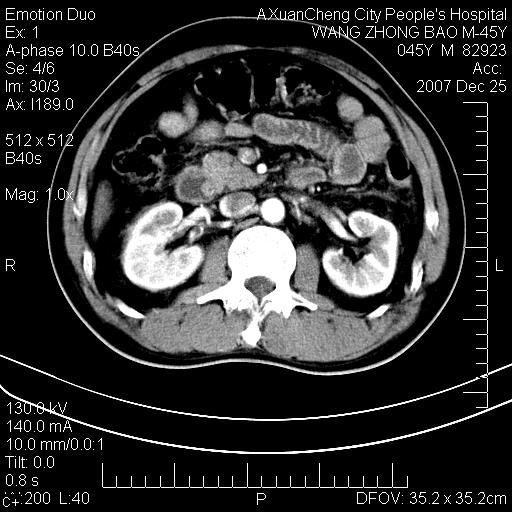

以下是引用qiuleiyu在2007-12-25 18:14:00的发言:[br]胰腺增大,周边渗出改变,肾前筋膜明显增厚,示少量积液.胆囊壁毛糙,周边少许渗出,胆总管壁厚,异常强化,然扩张不明显.结合病程急短;考虑;胆管炎,胆囊炎,胆源性胰腺炎可能大,请结合实验室检查及随访.

以下是引用lisihao在2007-12-25 14:23:00的发言:[br]急性水肿型胰腺炎[br]依据:1、胰腺弥漫性肿大,边缘稍毛糙;[br] 2、双侧肾周筋膜增厚,尤以左侧为甚(重要征象)[br] 3、双侧后胸膜增厚(刺激性炎症);[br] 4、结合病史,查血尿淀粉酶应该可以确诊。